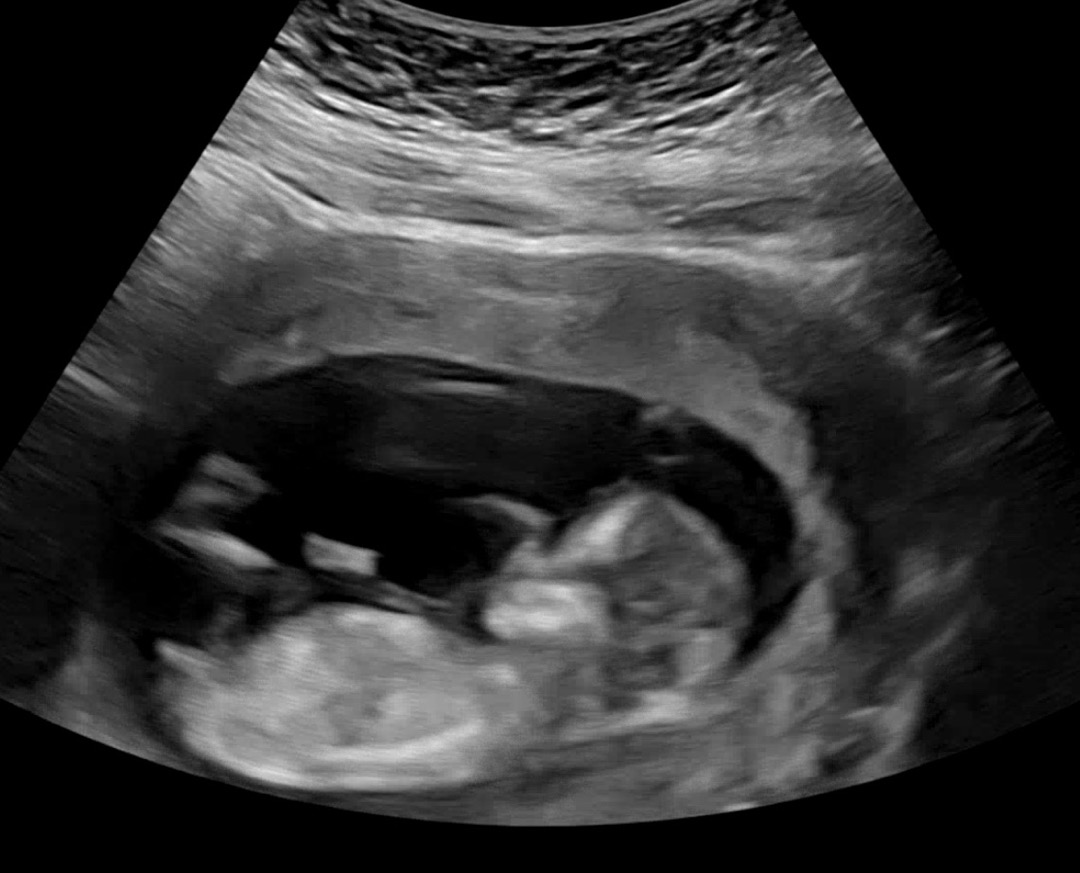

각도법 봐주실분.. 저 튀어나온거 ㄱㅊ 맞가요? ㅋㅋㅋㅋ

꼬리같기도 하긴 하네요 ㅠ고환이 안보여서